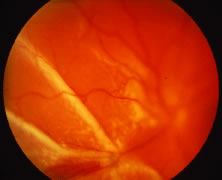

The ARN patient typically presents with progressive visual blurring in one or both eyes occurring over several weeks. These patients often are initially treated with corticosteroids, antitoxoplasmosis drugs, and other medications before arriving at the correct diagnosis. Examination reveals a prominent anterior uveitis that may be granulomatous or nongranulomatous (Fig. 1). Inflammatory signs may be prominent and cause severe pain (Fig. 2). The uveitis may be diffuse and so severe that it causes proptosis. These signs, and the diffuse vitreitis that makes the view of the retina difficult, may contribute to the high degree of delayed and/or misdiagnosis that occurs in the early stages of the disease. Significant vitreous cellular infiltration is seen in the presence of retinitis that is manifest by opacification of the retina, often most prominently in the periphery. Posterior pole involvement may include retinitis, as well as inflammation of the optic nerve head. Optic neuropathy might be the first sign of ARN with subsequent development of other retinal manifestations.8 Ultrasonography and computed tomography (CT) might be helpful in cases of ARN associated with optic nerve edema revealing enlargement of the optic nerve sheath.9 Even in ARN patients who are not immunocompromised and who have no clinical evidence of encephalitis, magnetic resonance imaging of selected cases has shown lesions of the lateral geniculate, optic tracts, and chiasma, which suggests that the virus spreads through the central nervous system (CNS) by axoplasmic transport from the retinal ganglion cells.10 A secondary retinal vasculitis is common, often accompanied by a mild number of retinal hemorrhages. Days to weeks after onset of the infection, the discrete peripheral lesions typically coalesce into a white or yellow ring of infected retina, and the associated vasculature is obliterated (Fig. 3). Necrotic retina desquamates into the vitreous resulting in vitreous sheets.3,6 Eventually, most untreated eyes can be expected to develop retinal detachment resulting from development of multiple full-thickness retinal breaks accompanied by traction or exudation.11 Giant retinal pigment epithelial tears have also been reported.12